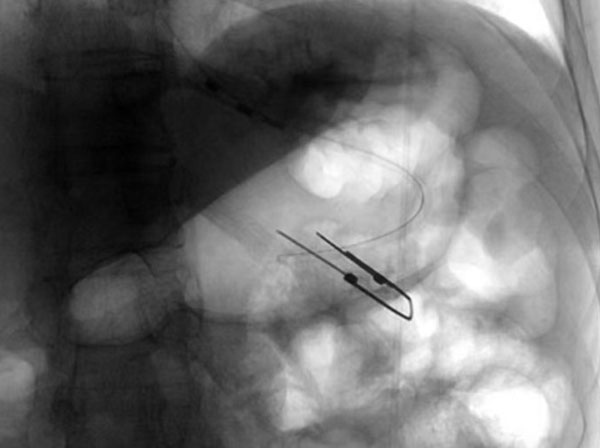

没有营养支持,患者无法进一步治疗,建立肠内营养通路迫在眉睫。放射科介入团队创新性提出全麻护航的手术方案,杨光主任与麻醉科沟通后,为患者制定了个体化镇静镇痛策略,同时采用联合DSA透视下的精准引导,快速将导丝及导管经口鼻迅速置入胃腔内,短时间内精准定位穿刺点,操作时间仅用15分钟。患者术中无不良反应,术后5分钟即恢复意识,造瘘管引流通畅,实现了全程无痛介入。